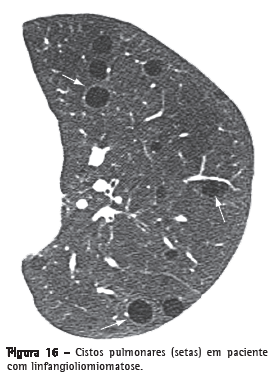

Cisto

Cisto é qualquer espaço arredondado, bem circunscrito, que é circundado por uma parede epitelizada ou fibrosa, de espessura variável.(29) Na TC, caracteriza-se por uma área arredondada de baixo coeficiente de atenuação no parênquima pulmonar com uma interface bem definida com o pulmão normal adjacente (Figura 16).(1,7) A espessura da parede do cisto pode variar, sendo normalmente fina (< 2 mm). Cistos geralmente contêm ar, mas, ocasionalmente, podem conter líquido (por ex.: cisto broncogênico) ou mesmo algum material sólido. Doenças que cursam geralmente com múltiplos cistos pulmonares incluem a linfangioliomiomatose, a histiocitose de células de Langerhans, a pneumonia intersticial linfocítica e a síndrome de Birt-Hogg-Dubé.(30,31)